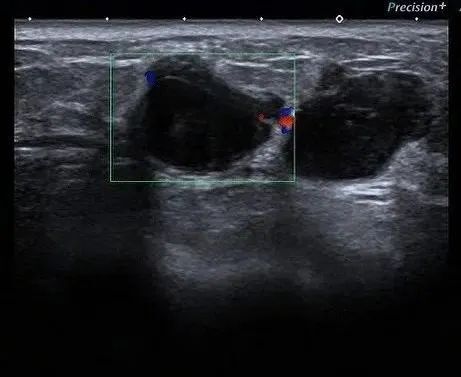

一旦彩超发现乳腺结节,就会根据乳腺结节的形状,进行一次面试进行评级,也即是对其的危险度进行评分,BI-RADS分级法将乳腺病变分为0~6级。

一般来说,级别越高,恶性的可能性越大。

边界比较清楚的、漂亮规整的会归类 2 级或 3 级,考虑为比较好的结节,危险性不高;

边界没那么清楚、不漂亮的、形状没那么规则的可能归为 4A 级,表示这个结节有点轻微的怀疑,需要进一步检查证明它是不是好结节。当然随着形态的不好,危险度的升高,还有 4B 级,4C 级,5 级,6 级的评分。

该分级主要从形态、方位、边缘、内部回声、后方特征、与周围组织关系、钙化等几方面描述乳腺肿物。

形态不规则、纵横比大于1、边缘模糊(成角、微小分叶、“蟹足状突起”)、不均质低回声、后方回声改变、结构紊乱侵犯周边组织、钙化均考虑为恶性标志。